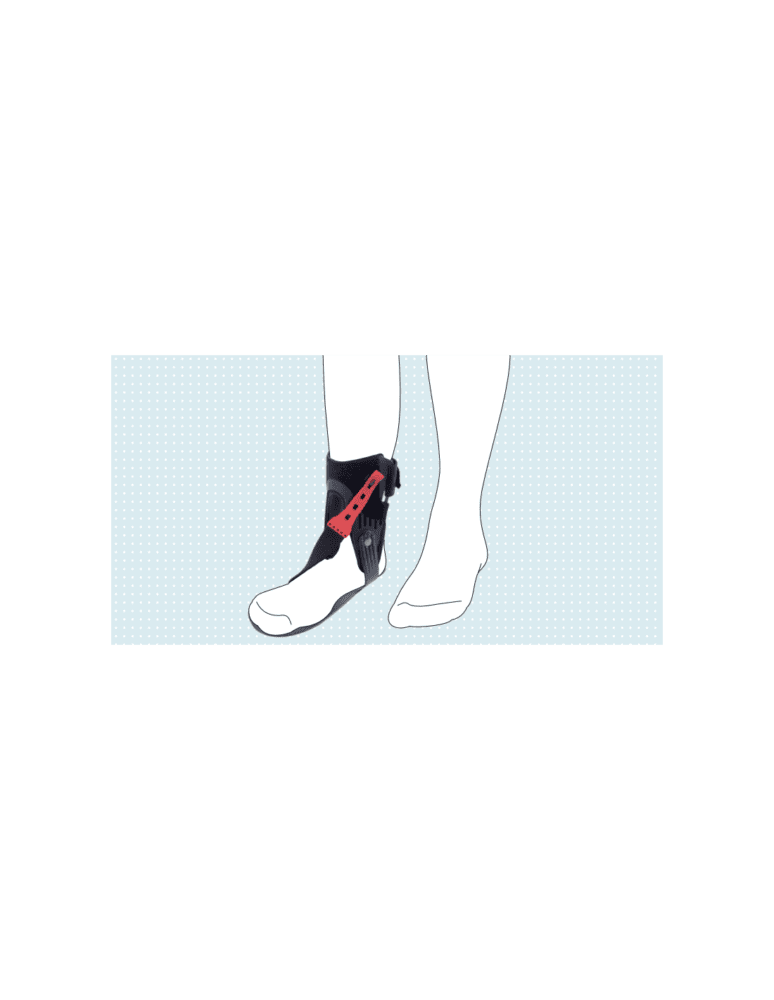

Orteza charakteryzuje się bardzo dobrym dopasowaniem do stawu skokowego oraz skuteczną stabilizacją dzięki zastosowaniu podwójnie skrzyżowanych taśm, anatomicznie ukształtowanych usztywnień z tworzywa sztucznego oraz innowacyjnego systemu sznurowania – BOA® Fit System. Dzięki temu systemowi, użytkownik ma możliwość stosowania różnego poziomu kompresji, czyli siły oddziaływania ortezy na staw skokowy. Regulacja odbywa się w sposób płynny, co zdecydowanie poprawia walory użytkowe wyrobu. BOA® Fit System funkcjonuje w oparciu o zespół zróżnicowanych poliamidowych przelotek, linek stalowych pokrytych tworzywem sztucznym oraz szpulowych pokręteł zapadkowych. Taka konstrukcja wyrobu bardzo poprawia wytrzymałość i walory użytkowe ortezy.